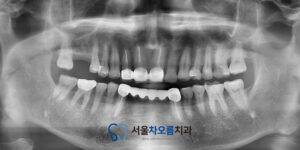

위 환자분께서는 처음 내원하실 때는

특별히 아프다기보다는 전체적으로

치료해야 할 곳들이 있어서 상담을

받아보고 싶다는 말씀을 하셨습니다.

검진 결과, 여러 부위에 걸쳐

치료가 필요한 상태였는데요.

우선 눈에 띄었던 것은 오른쪽 위 큰 어금니가

완전히 탈락된 상태였습니다.

해당 부위는 세마역임플란트 치료가 필요한 상황이었고,

그 주변의 다른 치아들 역시 상태가 좋지 않았습니다.

오른쪽 위 맨 안쪽 큰 어금니와

왼쪽 위 작은 어금니,

큰 어금니 모두 충치가

상당히 진행되어 신경치료가

필요한 상황이었습니다.

또한 하악, 즉 아래턱 쪽의 경우에는

왼쪽 아래 큰 어금니의 뿌리 쪽에

염증이 생긴 상태로 확인되어,

이 역시 신경치료가 불가피했습니다.

반면, 오른쪽 아래 맨 안쪽 큰 어금니는

충치가 있긴 했지만 신경까지는 침범하지

않은 상태였기 때문에, 이 부위는

온레이 치료로 보존하기로 했습니다.